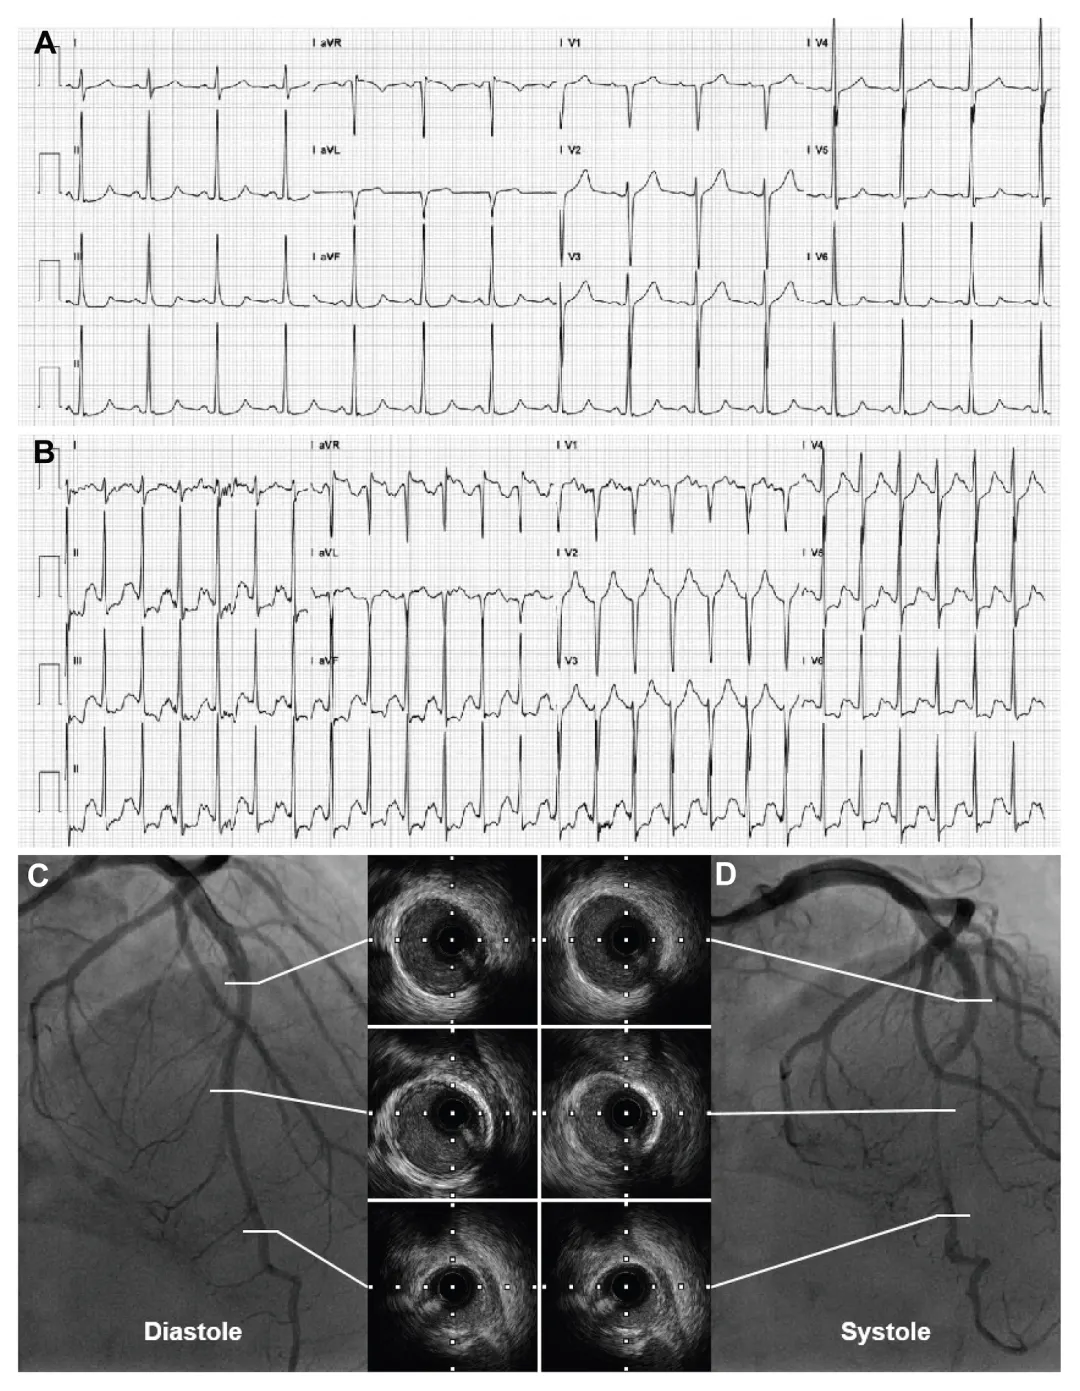

图1:心电图、左前降支冠状动脉造影

图及血管内超声(IVUS)图像

(A) 十二导联标准心电图显示静息状态下ST段存在非特异性偏移。(B) 运动时,在II、III、aVF导联以及V4至V6导联出现显著的ST段压低。(C) 和 (D) 展示了左前降支冠状动脉造影的典型特征,以及舒张期和收缩期相关节段的血管内超声(IVUS)图像。

患者在进行运动心电图测试时,出现了非典型的ECG变化,包括在II、III、aVF和V4至V6导联中出现显著的ST段压低。

尽管运动心电图显示缺血迹象,但患者的常规休息ECG、超声心动图

和心脏生物标志物(如心肌肌钙蛋白

T和N末端前B型利钠肽)均在正常范围内。